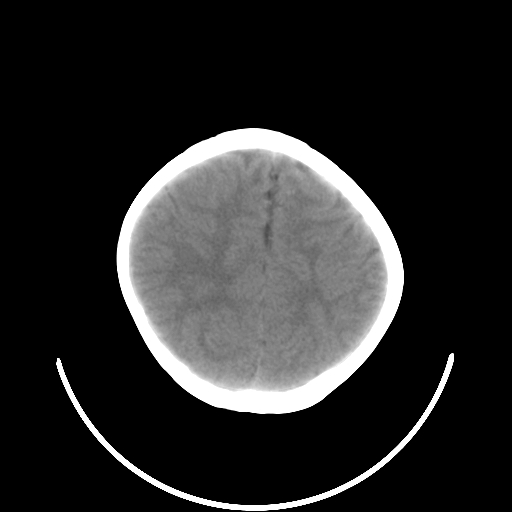

以下是引用深泽交通医院在2009-10-16 8:25:00的发言:[br]右眼环出血伴异物

以下是引用卜一在2009-10-16 15:01:00的发言:[br]右眼球挫裂伤伴异物!

以下是引用拾荒者在2009-10-17 18:38:00的发言:[br]鼻面部皮下积气,右侧睑缘及眼球壁高密度异物影,左侧眼球壁晶状体内侧缘处是圆形低密度影。低密度异物?应提请眼科医生注意。